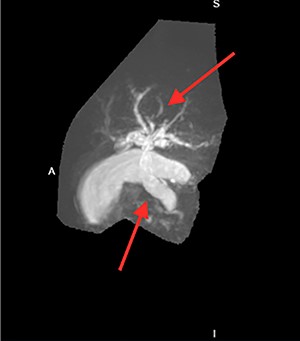

Many imaging studies can be used to diagnose annular pancreas. Upper gastrointestinal series may show an obstruction with proximal dilation. Computerized tomography (CT) scans may show a complete or partial ring of tissue surrounding the duodenum. Magnetic resonance cholangeopancreatography (MRCP) may show dilation of intrahepatic and/or extrahepatic bile ducts and possibly obstruction of bile flow (Figure 2). Endoscopic retrograde cholangiopancreatography (ERCP) is the diagnostic modality of choice and may show duodenal compression due to annular pancreas [4].

He had an ultrasound (US) and CT abdomen/pelvis showing abnormal intra and extra hepatic biliary ductal dilatation, suspicious for obstruction (Figs. 1 and 2). He then had an MRCP showing ductal dilation with no obvious filling defect. The total bilirubin, direct bilirubin and lipase was normal at 0.4 miligrams per deciliter (mg/dl), 0.1 mg/dl and 38 units per liter (unit/L), respectively. Liver function tests were within normal limits.